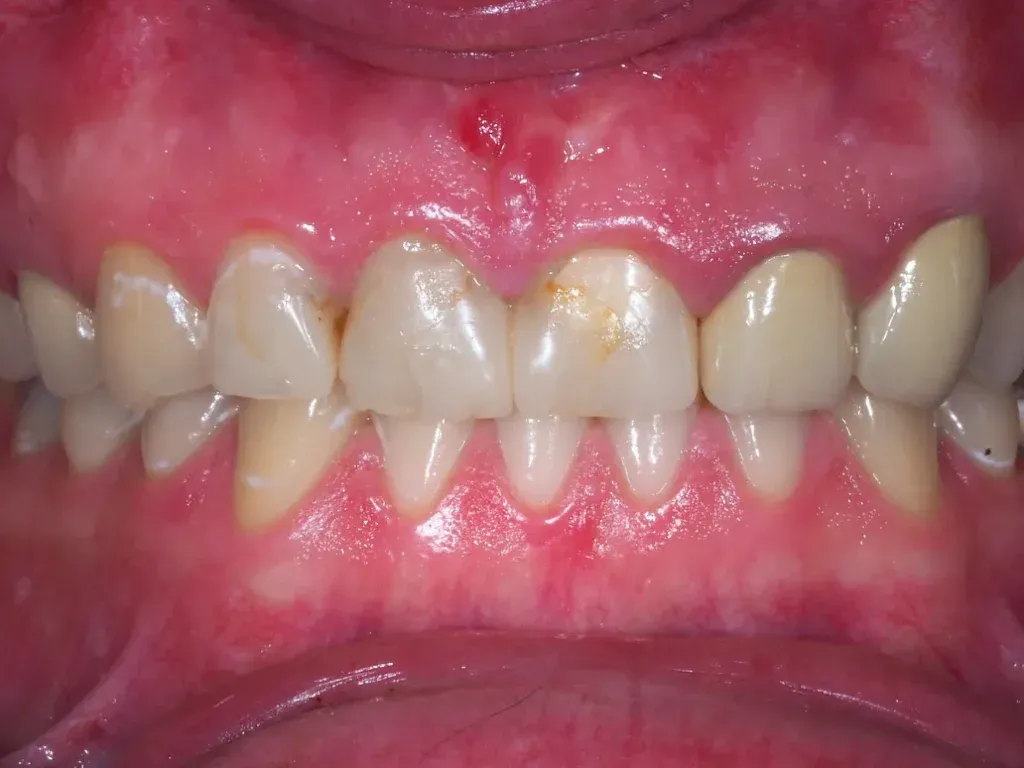

Jednymi z pierwszych i najbardziej widocznych objawów zapalenia dziąseł są ich zaczerwienienie i obrzęk. Zauważysz, że zdrowe, bladoróżowe dziąsła zmieniają swój kolor na jasnoczerwony, a nawet fioletowy. Stają się również spuchnięte i powiększone, co jest wyraźnym sygnałem toczącego się stanu zapalnego. To reakcja tkanek na obecność bakterii i toksyn, które podrażniają delikatną błonę śluzową.Krwawienie podczas szczotkowania dlaczego to nie jest normalne?

Jeśli Twoje dziąsła krwawią podczas codziennego szczotkowania zębów, nitkowania, a nawet jedzenia twardych pokarmów, to jest to absolutnie kluczowy sygnał alarmowy. Wiele osób myśli, że to normalne, zwłaszcza przy mocniejszym szczotkowaniu, ale to mit! Zdrowe dziąsła nie krwawią. Krwawienie jest oznaką stanu zapalnego i uszkodzenia naczyń krwionośnych w dziąsłach. Nigdy nie powinno być ignorowane, ponieważ świadczy o problemie, który wymaga uwagi.

Jak już wspomniałam, zdrowe dziąsła mają bladoróżowy kolor. W przypadku zapalenia, ich barwa może zmieniać się od jasnoczerwonej, przez ciemnoczerwoną, aż po fioletową. Dodatkowo, zmienia się ich kształt zamiast przylegać ściśle do zębów, stają się obrzęknięte, zaokrąglone na brzegach i mogą wyglądać na "napompowane". To wyraźny wskaźnik, że coś jest nie tak z ich kondycją.